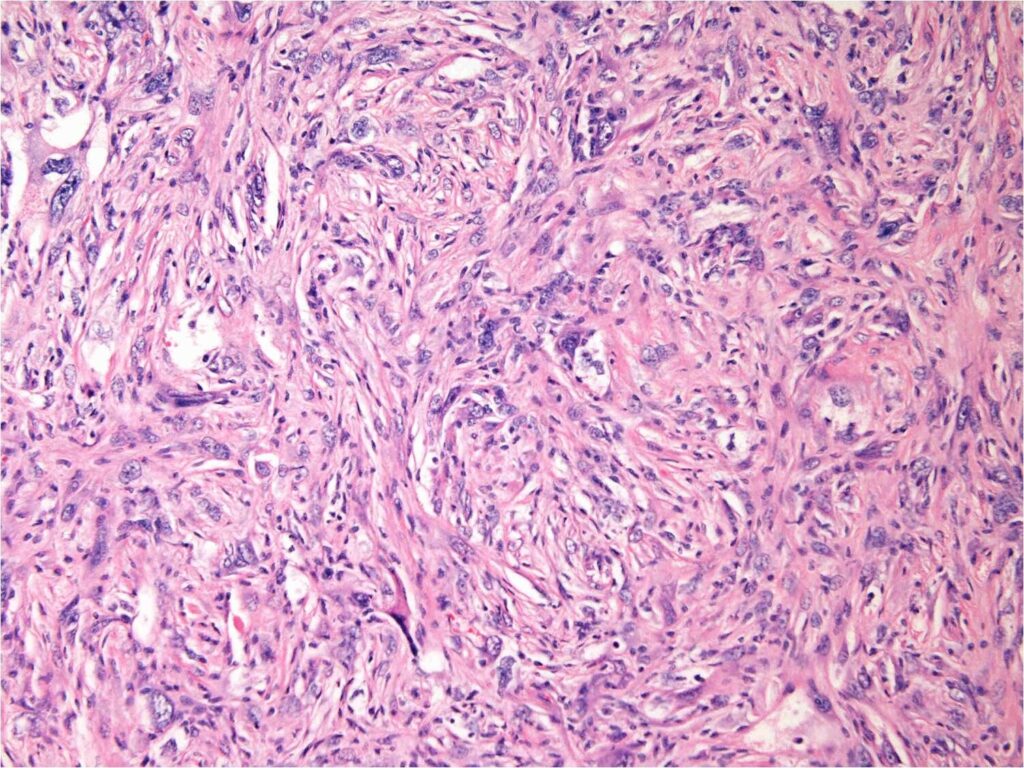

Malignant fibrous histiocytoma of bone is a high-grade spindle cell sarcoma. Microscopically they are heterogeneous fibroblastic tumors formed by poorly differentiated fibroblasts, myofibroblasts, histiocyte-like cells with high degree of pleomorphism, characteristic storiform pattern and also demonstrate bizarre multi-nucleated giant cells (Fig. 7-9).

Fig. 7-9: Microscopic Pathology. Low (Fig. 7), intermediate (Fig. 8) and high (Fig. 9) power magnification H&E slides demonstrate a hypercellular high grade spindle cell sarcoma. Abundant poorly differentiated fibrous tissue is visible in storiform pattern in all magnifications. Multiple giant cells are also seen. Tumor cells are pleomorphic and darkly stained. There are large bizarre appearing cells and atyipical mitotic figures.